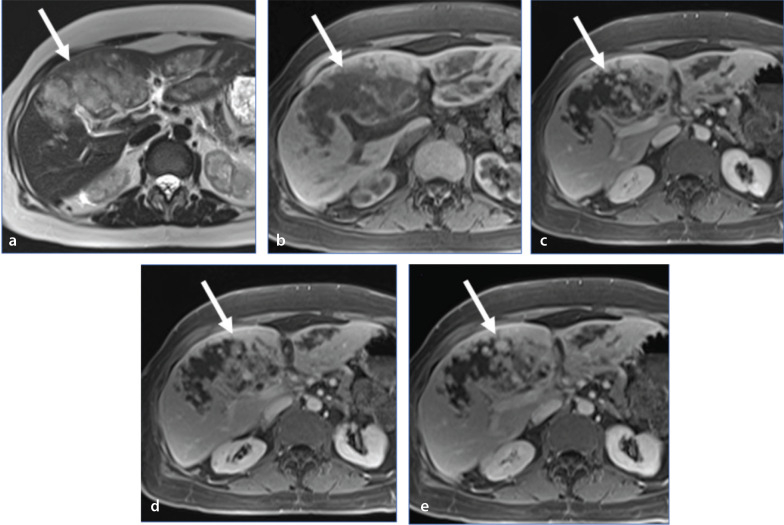

肝脏的非肿瘤样病变可能与肝肿瘤相似。在许多情况下,需要进行活组织检查以确认病理。不过,有几种肿瘤样病变可以得到正确诊断或前瞻性建议,从而使患者免于不必要的焦虑和花费。在这篇以图像为重点的综述中,我们介绍了八个此类实体的超声、计算机断层扫描、磁共振成像和正电子发射断层扫描特征。讨论了提示正确病理的线索,并描述了通常的临床环境。许多此类病变的治疗方法与真正的肿瘤不同,在介绍的许多病例中还讨论了当前的治疗方案。阅读完本文后,读者将对这些病变有更好的了解,并知道在哪些情况下应将其纳入鉴别诊断。

Non-neoplastic tumor-like conditions of the liver can appear similar to hepatic neoplasms. In many cases, a biopsy is required to confirm the pathology. However, several tumor-like conditions can be correctly diagnosed or suggested prospectively, thus saving patients from unnecessary anxiety and expense. In this image-focused review, we present the ultrasound, computed tomography, magnetic resonance imaging, and positron emission tomography scan features of eight such entities. Clues that indicate the correct pathology are discussed, and the usual clinical setting is described. Many of these lesions are treated differently from true neoplasms, and the current treatment plan is discussed in many of the cases presented. After reviewing this article, the reader will have a better understanding of these lesions and the situations in which they should be included in the differential diagnosis.